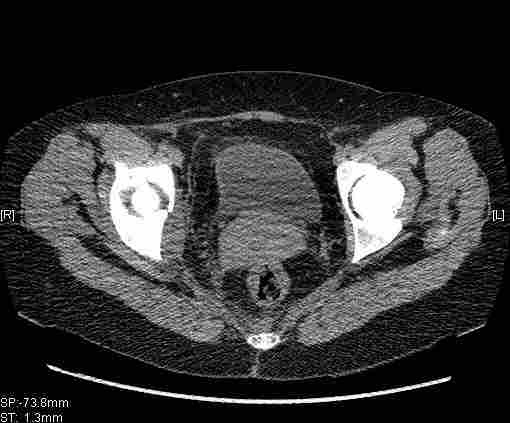

Re: Т-образный перелом вертлужной впадины

Удалось сегодня вывести пациентку в соседнюю больницу, где есть кт. Срезы сделаны только горизонтальные.